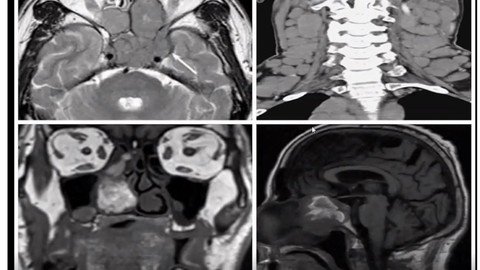

This Course Prepares the student in CENTRAL NERVOUS SYSTEM (Sutton) Chapter for Radiology Exams.

6. Central Nervous and Head & Neck